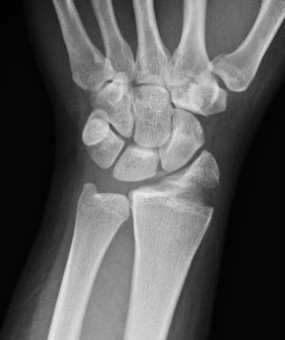

Xray

Dorsal radiocarpal dislocation with dorsal rim fracture

Dorsal radiocarpal dislocation with radial styloid fracture